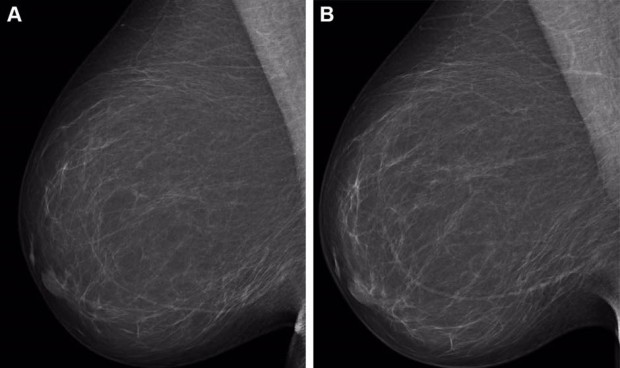

La combinación de sistemas de inteligencia artificial (IA) para el riesgo de cáncer de mama a corto y largo plazo da como resultado una mejor evaluación del riesgo de cáncer, según un estudio publicado en 'Radiology', una revista de la Sociedad Radiológica de Norteamérica (RSNA). La mayoría de los programas de detección del cáncer de mama adoptan un enfoque único y siguen los mismos protocolos a la hora de determinar el riesgo de por vida de una mujer de desarrollar cáncer de mama. El uso de modelos de aprendizaje profundo basados en mamografías puede mejorar la precisión de la evaluación del riesgo de cáncer de mama y también puede conducir a diagnósticos más tempranos.

Existen diversas herramientas de IA para ayudar a detectar el riesgo de cáncer. Los modelos de diagnóstico de IA están entrenados para detectar lesiones sospechosas en las mamografías y son muy adecuados para estimar el riesgo de cáncer de mama a corto plazo. Más adecuados para el riesgo de cáncer de mama a largo plazo son los modelos de IA de textura, capaces de identificar la densidad mamaria. Las mujeres con un tejido mamario denso corren un mayor riesgo de desarrollar cáncer de mama y pueden beneficiarse de un cribado suplementario mediante resonancia magnética.

Para este estudio, el equipo de investigación trató de identificar si una herramienta de IA de diagnóstico disponible en el mercado y un modelo de textura de IA, entrenados por separado y posteriormente combinados, pueden mejorar la evaluación del riesgo de cáncer de mama. Utilizaron la herramienta de diagnóstico por IA Transpara y un modelo de textura desarrollado por ellos. Para entrenar los modelos se utilizó un conjunto de entrenamiento holandés de más de 39.000 exámenes. Los modelos de riesgo a corto y largo plazo se combinaron mediante una red neuronal de tres capas.

El modelo combinado de IA se probó en un grupo de estudio de más de 119.000 mujeres que se incluyeron en un programa de cribado de cáncer de mama en la Región Capital de Dinamarca entre noviembre de 2012 y diciembre de 2015. La edad media de las mujeres era de 59 años.

En comparación con los modelos de diagnóstico y textura por sí solos, el modelo combinado de IA mostró una mejora general en la evaluación del riesgo tanto para la detección de cáncer de intervalo como a largo plazo. Los cánceres de intervalo son aquellos que se detectan entre las revisiones rutinarias. El modelo también permitió identificar a las mujeres con alto riesgo de cáncer de mama. El 44,1 por ciento de los cánceres de intervalo y el 33,7 por ciento de los cánceres de larga duración correspondían a mujeres identificadas por el modelo combinado con el 10 por ciento de mayor riesgo combinado.